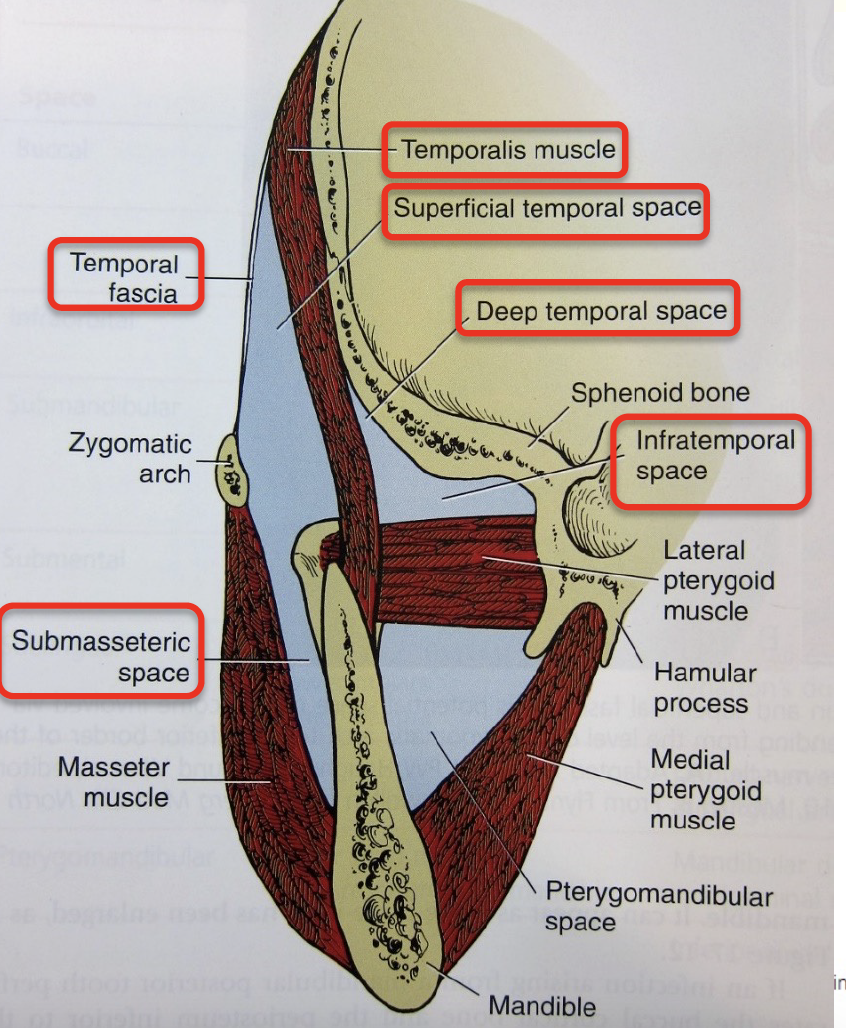

Masticator space

Temporal space

Temporalis m.分隔

- Superficial temporal space

- Deep temporal space

Infratemporal space

Zygomatic arch 以下

- 外側

- Temporalis

- 內側

- Pterygoid plate

- Maxillary a.

Pterygomandibular space

Med. pterygoid m.外

- Inf. alveolar a./ v./ n.

- Lingual n.

Submassetric space